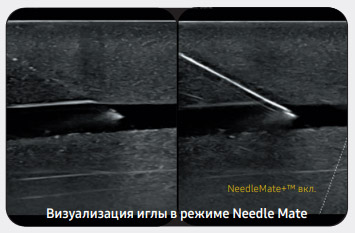

Четкое отображение кончика иглы

Функция NeedleMate+™ помогает точно определить положение кончика иглы, например при проведении нервной блокады. Высокая точность и эффективность процедуры достигаются за счет добавления к данной функции технологии управления лучом.